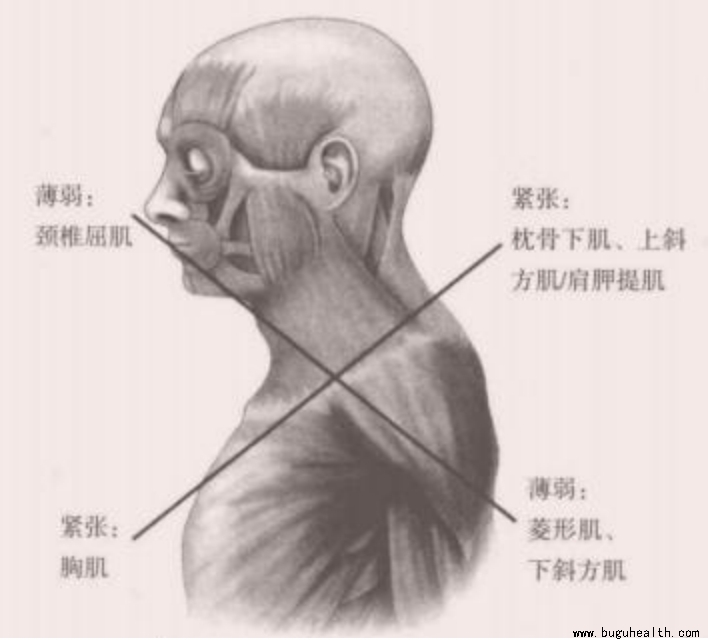

我们举例来讲,上交叉综合征是紧张的背侧的上斜方肌、肩胛提肌,以及腹侧的胸大肌和胸小肌相互交叉,薄弱的前侧的深层屈肌和中下斜方肌相交叉,这时候我们做挺胸抬头的动作时总感觉格外费力,而含胸时则反而轻松了,当我们继续延续这种不正确的体态,就会形成恶性循环,薄弱的肌肉越来越薄弱,紧张的肌肉越来越紧张,当我们想要改善的时候,如果只是去增强薄弱的肌肉,那么就不得不去额外克服紧张肌肉带来的阻力,那么训练效果就会收到影响,所以我们可以先去将紧张的肌肉进行拉伸,那么训练薄弱的肌肉时,肌肉的激活和启动就会更快更省力,就会达到事半功倍的效果了。

关于上交叉,日常的驼背探颈等习惯使得斜方肌上束、斜角肌、胸锁乳突肌紧张,使得颈部压力变大,出现疼痛。